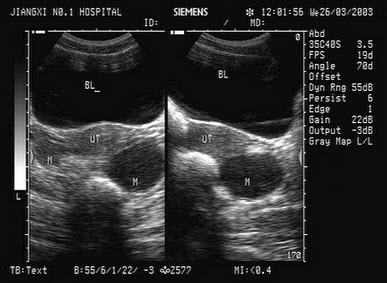

38、单项选择题

女性,40岁,反复下腹部疼痛、白带异常3年余。超声检查如图,最可能的诊断为()

A.输卵管积液

B.囊腺瘤

C.畸胎瘤

D.子宫肌瘤

E.附件囊肿